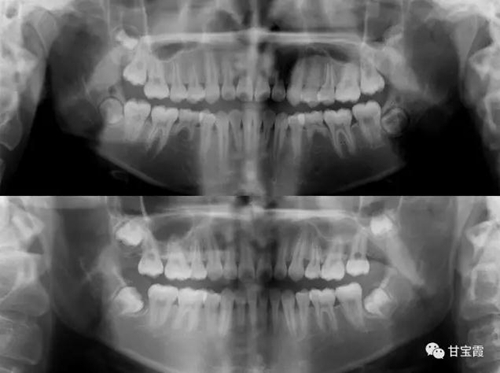

下面這兩張X片子就是矯正前后的對(duì)比,看不出下頜缺牙

5.jpg